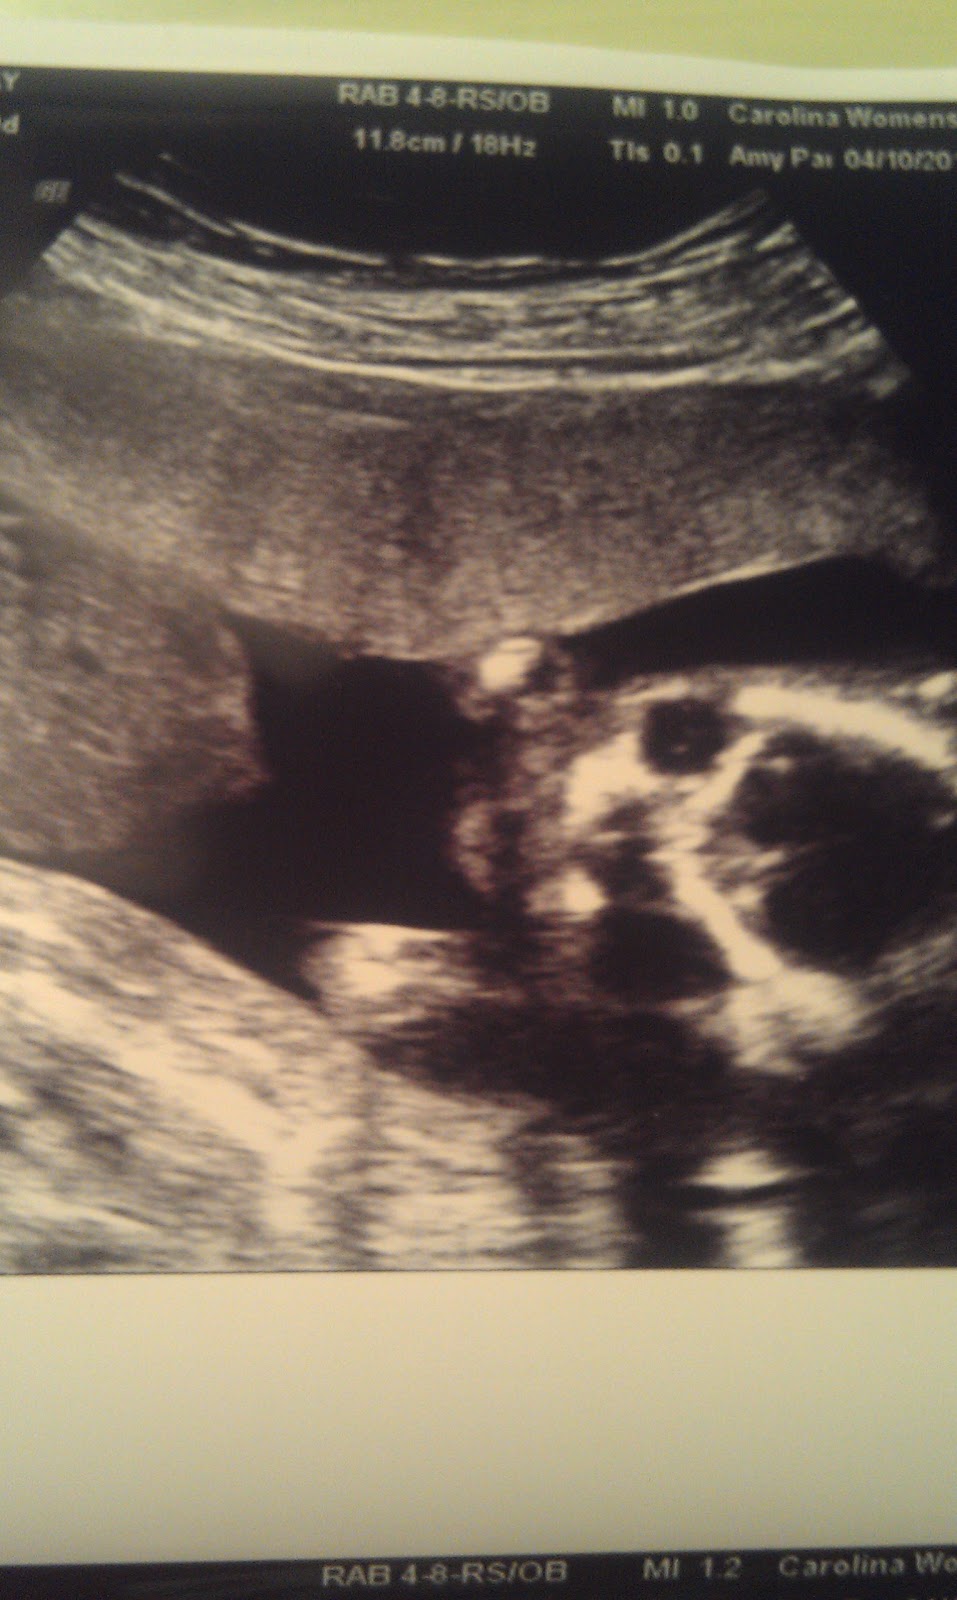

Today was our big ultrasound for Miss Charlotte. Of course, we already knew she was a girl. She made that quite clear a few weeks ago. Today, though, I was anxious to be sure all was well everywhere else. We saw the 4 chambers of her heart, her kidneys, her bladder, tummy, cute little feet, and she was not going to let us get a profile of her face. She was much too comfy with her hands up by her face. She kept turning her face away from us instead of turning so we could get the profile shot. She is a busy little wiggle worm and kept the ultrasound tech. working trying to see everything.

One thing we couldn't get a clear look at at first was her umbilical cord. Finally, we were able to see it, and we found out that she does not have the typical 3 vessel (one artery, 2 veins) cord. She has a two vessel cord - one artery, one vein. If you would like to know what that means biologically, Google it - and read it from a medical website. Basically, it means instead of two veins taking blood away from the baby back to me, there is only one doing that. The artery is still doing it's job....taking blood to the baby. So one going in, one going out...instead of two going out. This can mean different things in different situations. A lot of time it is an implication of chromosomal abnormalities. However, I've already undergone that testing, and she is very low risk for any chromosomal abnormalities (she scored even lower than Collen did). The main thing we will be watching is her growth, movement, and fluid. I will go in for more frequent ultrasounds, and we will keep track of how she is growing. So far, she is right on target and looks great anatomically. All of her organs look good...we couldn't see her hands (just fists), but I did see five toes on each foot. Everything looks good....just going to have to monitor her more closely.

Some pictures we were able to get from our little wiggle worm...

Face

Sweet little foot :)